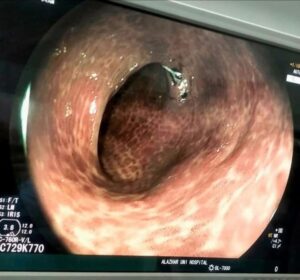

أعاد الدكتور هاني عوض الله، استشاري الجهاز الهضمي والكبد، نشر صورة طبية حقيقية تُظهر قولون مريض استخدم الملينات لفترة طويلة، مؤكدًا أن هذه ليست حالة نادرة كما يظن البعض، بل باتت تتكرر في عيادته مع العديد من المرضى الذين يعتمدون على الملينات بشكل مزمن دون استشارة طبية.

وقال الدكتور عوض الله إن ما يراه الأطباء داخل غرف المناظير أصبح “جرس إنذار” خطير، يوضح أن الملينات ليست وسيلة آمنة لإنقاص الوزن أو تنظيم الإخراج كما يروج البعض، وأن الإفراط فيها قد يؤدي إلى شلل وظيفي للقولون وتحوله إلى ما يشبه “كيس بلاستيكي متضخم” عاجز عن الحركة.